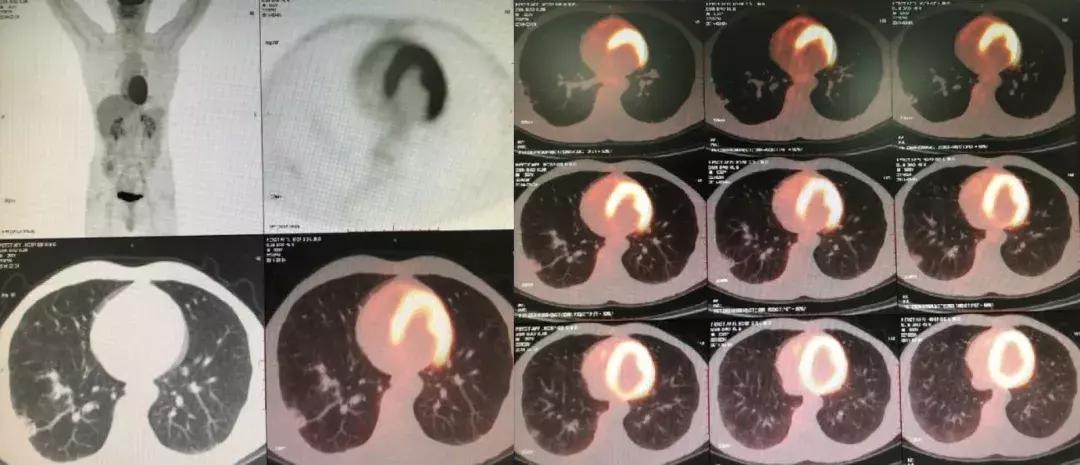

随访:活动性呼吸困难逐渐加重,出现了气胸

由于儿子反复治疗的花销已经很大了,这位患者诊断后没有特别治疗,曾去过多家医院,考虑过肺移植,但由于是遗传性疾病只好作罢。随后在我院随访,呼吸困难逐渐加重,间质改变越来越严重,原来是上肺比较明显,后来下肺病变也加重了,再后来右上肺出现大泡,最后出现气胸,反复住院,这个患者后来再也没有来了……

胸部CT(2017-07-11):

胸部CT(2018-02-22):